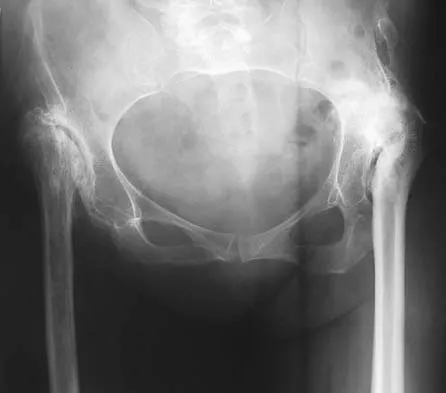

The mother of a 26-month-old boy reports that he has been unwilling to bear weight on his left lower extremity since he awoke this morning. She denies any history of trauma. He has a temperature of 99.4 degrees F (37.4 degrees C), and examination reveals that abduction of the left hip is limited to 30 degrees. Laboratory studies show a WBC of 11,000/mm3 and an erythrocyte sedimentation rate of 22 mm/h. A radiograph of the pelvis is shown in Figure 13. Management should consist of

Explanation

The most likely diagnosis is transient synovitis. Initial management should consist of bed rest and serial observation to rule out atypical septic arthritis of the hip. In an unreliable family situation, hospitalization for bed rest and observation may be indicated. Other disorders such as proximal femoral osteomyelitis, leukemia, juvenile rheumatoid arthritis, pelvic osteomyelitis, diskitis, and arthralgia secondary to other inflammatory disorders should be considered. However, these disorders are unlikely because of the paucity of abnormal clinical signs exhibited by the patient. On the other hand, transient synovitis of the hip in children is a diagnosis of exclusion; other possibilities should be explored if the patient's symptoms do not follow a typical course and resolve in 4 to 21 days.